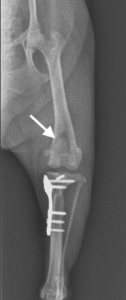

上の画像は術後のX線画像です。膝蓋骨が正しい位置へ矯正され、脛骨高平部が計画通りの角度になるよう骨切り・水平化が行われ、特殊な形をしたプレートで固定されています。これにより骨と筋肉の位置関係が正しい位置へ矯正され、患肢へかかる力学的な方向も垂直方向へと変化し、しっかりと足に体重をかけることが出来るようになります。

こちらの症例は矢印で示した左膝蓋骨内方脱臼に加え、前十字靭帯断裂を併発しています。膝蓋骨を正しい位置へ矯正するため、骨の掘削や関節包を縫縮める手技を行います。さらに、TPLOと呼ばれる脛骨近位部分の骨切り・水平化・固定する主義を行うことにより、脛骨へかかる力学的な方向を変化させ、膝関節の安定化をはかります。

TPLOで骨切りする骨の大きさや回転させる距離は、体重や骨の大きさ・脛骨高平部の角度により完全に計算されており、いかに正しい計算をして治療計画を立てられるか、また計画通りに緻密な手術を実施できるかがとても重要となります。